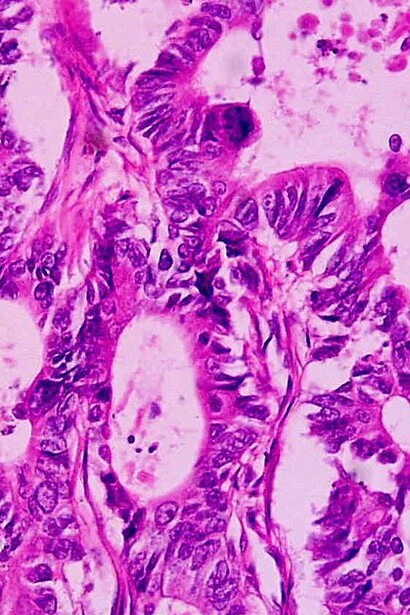

El éxito de las inmunoterapias contra el cáncer se basa en la selección de neoepítopos (antígenos asociados a tumores) altamente expresados. Estas terapias favorecen preferentemente a las neoplasias malignas con una elevada carga mutacional. Aquí demostramos que las respuestas tempranas de los interferones de tipo I median el éxito de los inhibidores de puntos de control inmunitario, así como la propagación de epítopos en tumores poco inmunogénicos, y que estas respuestas de interferones pueden potenciarse mediante la administración sistémica de partículas lipídicas cargadas con ARNm que codifica antígenos no específicos del tumor.

En ratones, las respuestas inmunitarias de los tumores sensibles a los inhibidores de puntos de control fueron transferibles a tumores resistentes y dieron lugar a una mayor inmunidad con propagación antigénica que protegió a los animales de una nueva exposición al tumor. Los hallazgos muestran que la resistencia de los tumores a la inmunoterapia viene dictada por la ausencia de una respuesta al daño, que puede restaurarse potenciando las respuestas tempranas de los interferones de tipo I para permitir la propagación de epítopos y respuestas autoamplificadoras en tumores refractarios al tratamiento.

Los inhibidores de puntos de control inmunitarios (PCI) han revolucionado el tratamiento del cáncer. Al bloquear las vías que regulan el sistema inmunitario, estos anticuerpos monoclonales pueden mejorar la inmunidad, potenciar la actividad de las células T y reiniciar el reconocimiento y la destrucción de las células cancerosas. El éxito de la terapia con PCI se basa en una respuesta de las células T activadas contra los neoepítopos cancerosos, lo que favorece preferentemente a las neoplasias malignas con una alta carga mutacional tumoral (CMT). Sin embargo, muchos tumores con alta CMT son resistentes a los PCI y los cánceres con baja CMT pueden tener un número limitado de pacientes que responden al tratamiento. La interacción que impulsa la inmunogenicidad del cáncer y la respuesta a la inmunoterapia sigue sin entenderse bien.

Muchos tumores logran desarrollar resistencia a los PCI al secuestrar las vías de señalización del IFN tipo I (IFN-I), frustrando así la inducción de la inmunidad terapéutica. La producción sostenida de IFN-I puede precipitar un estado inmunorregulador y un entorno inflamatorio crónico perjudicial para la inmunidad adaptativa y la respuesta a los PCI. Sin embargo, el IFN-I es vital para la respuesta inmunológica a través de la activación de los receptores de reconocimiento de patrones y desempeña un papel fundamental en la facilitación de las interacciones entre las células dendríticas y las células T efectoras. Basándose en estos efectos, se planteó la hipótesis de que el IFN-I temprano es fundamental para iniciar la inmunoterapia contra el cáncer y la propagación de epítopos en neoplasias malignas inmunogénicas, y podría inducirse artificialmente mediante biomiméticos codificadores de ARN en tumores poco inmunogénicos.

Descubrimos que el IFN-I temprano determinaba la magnitud de la respuesta a los PCI en tumores sólidos murinos tanto intracraneales como extracraneales y dictaba la inmunogenicidad del cáncer en tumores que respondían a los PCI de una manera que era transferible a neoplasias malignas previamente resistentes. Este conocimiento contribuyó al desarrollo de vacunas de ARN mensajero no específicas para tumores que restauraban la inmunidad dependiente del IFN-I en modelos paralelos para tumores resistentes a los PCI, lo que permitía la propagación de epítopos y mejoraba la supervivencia.

El estudio demostró que las respuestas tempranas de los interferones de tipo I median el éxito de los inhibidores de los puntos de control inmunitario, así como la propagación de epítopos en tumores poco inmunogénicos. Estas respuestas de los interferones pueden potenciarse mediante la administración sistémica de partículas lipídicas cargadas con ARN que codifica antígenos no específicos del tumor. En ratones, las respuestas inmunitarias de los tumores sensibles a los inhibidores de puntos de control fueron transferibles a tumores resistentes y mejoraron la inmunidad con la propagación antigénica que protegió a los animales de una nueva exposición al tumor. Estos resultados demostraron que la resistencia de los tumores a la inmunoterapia está controlada por la ausencia de una respuesta al daño, que puede restaurarse potenciando las respuestas tempranas del interferón tipo I para permitir la propagación de epítopos y las respuestas autoamplificadoras en tumores refractarios al tratamiento.